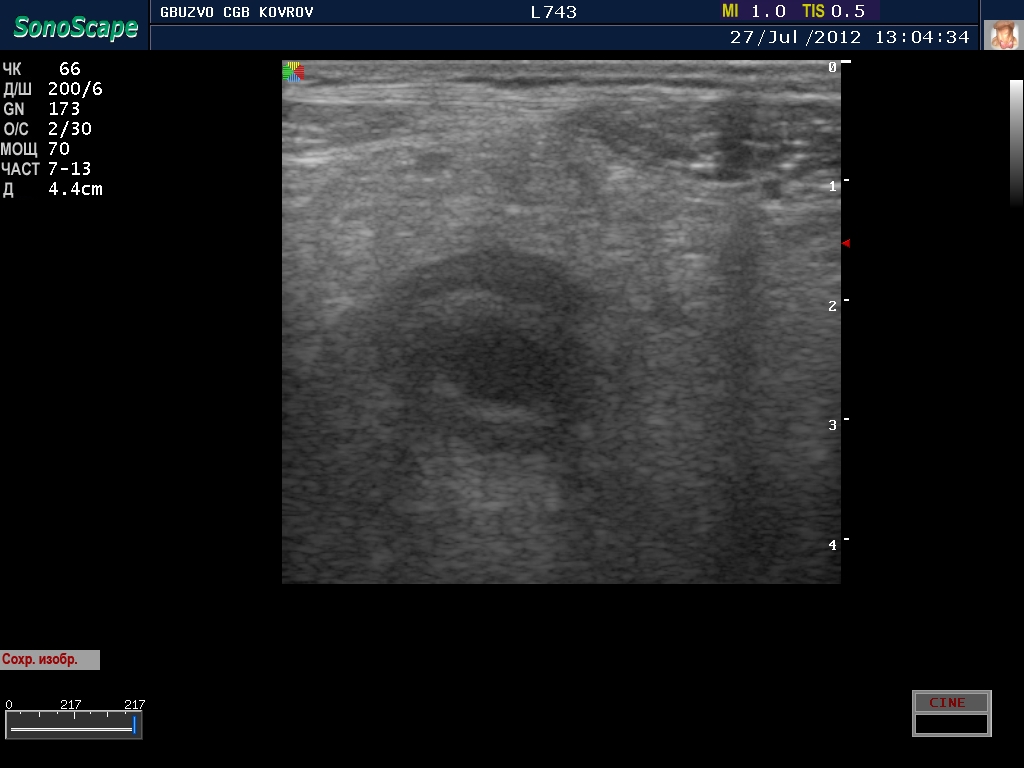

полечили два дня в гастроэнтерологии...состояние ухудшилось, узи контроль----->

Что это такое? Кишка?

ну, скажем так, часть кишечника :D

поподробнее? :shock: бодимаркер находится в правой подвсздошной области, я бы подумал про аппендикс 8-)